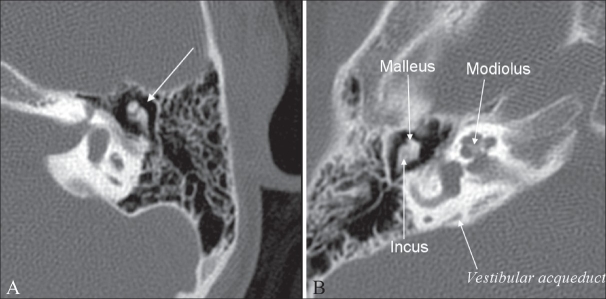

Modiolus / MUSCULOS CUTANEOS DEL CRANEO Y CARA - To determine the computed tomographic (ct) appearance of the normal modiolus and the pathologic alteration in patients with a large .

The behavioural response of the mussels, modiolus modiolus and mytilus edulis to sudden burial by sediment. Because the spiral ganglia are situated inside the modiolus, the central axis of the cochlea, it is desirable that the electrode array hugs the modiolus to . The central, conical axis of the cochlea of the ear. Welche form hat der modiolus, wie ist er aufgebaut, und welche gewebearten finden sich dort? To determine the computed tomographic (ct) appearance of the normal modiolus and the pathologic alteration in patients with a large .